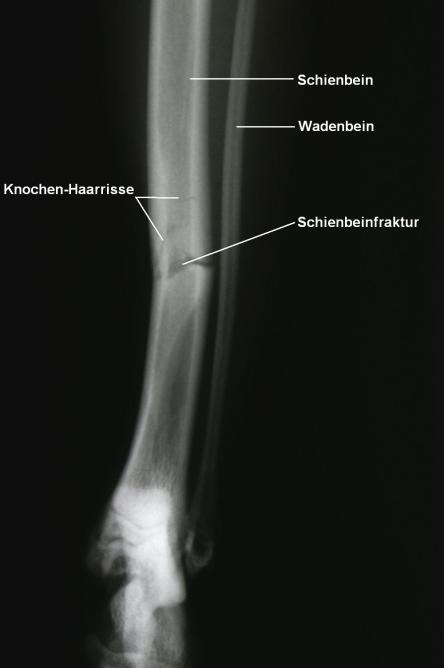

Auf dem Röntgenbild des Beines ist erkennbar, dass das Schienbein in der Mitte quer gebrochen ist. Feine Haarrisse ziehen von der Frakturspalte kniewärts. Das Wadenbein ist intakt, was die relative Stabilität des Bruchs erklärt.